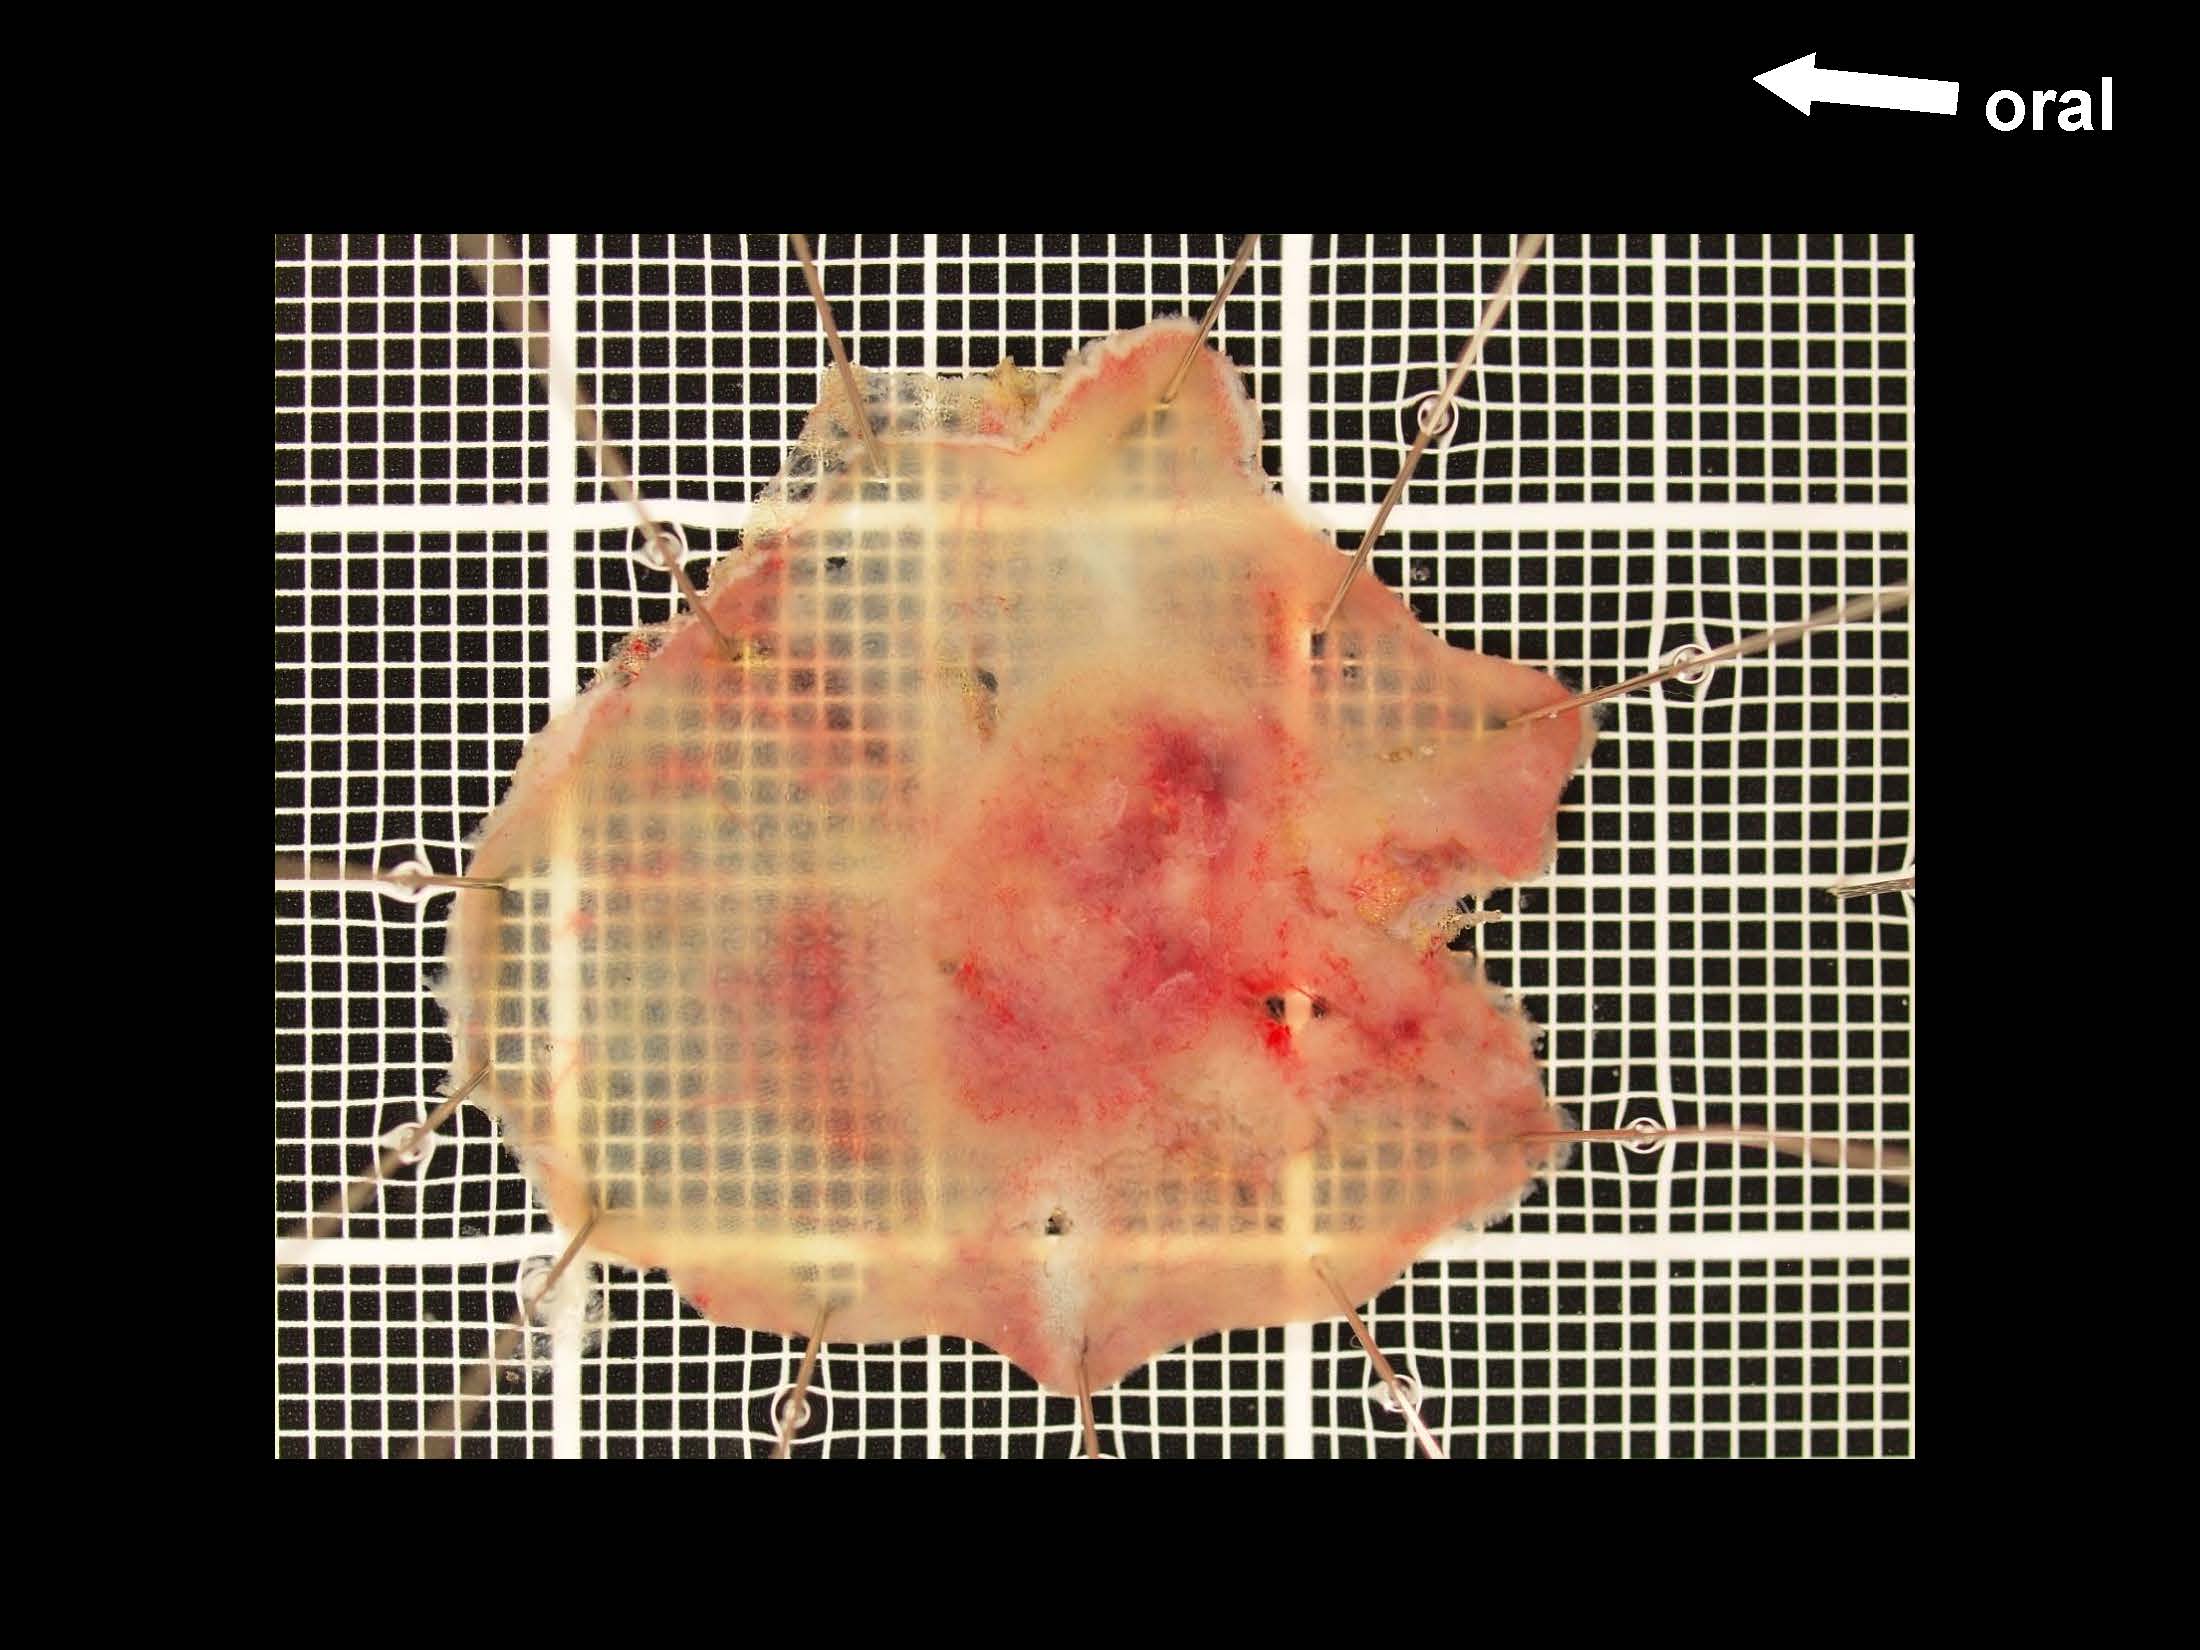

消化管Mapping~大腸~ 2021.10.27

消化管Mapping~大腸~

消化管Mapping

全ページPDFのダウンロードはこちら